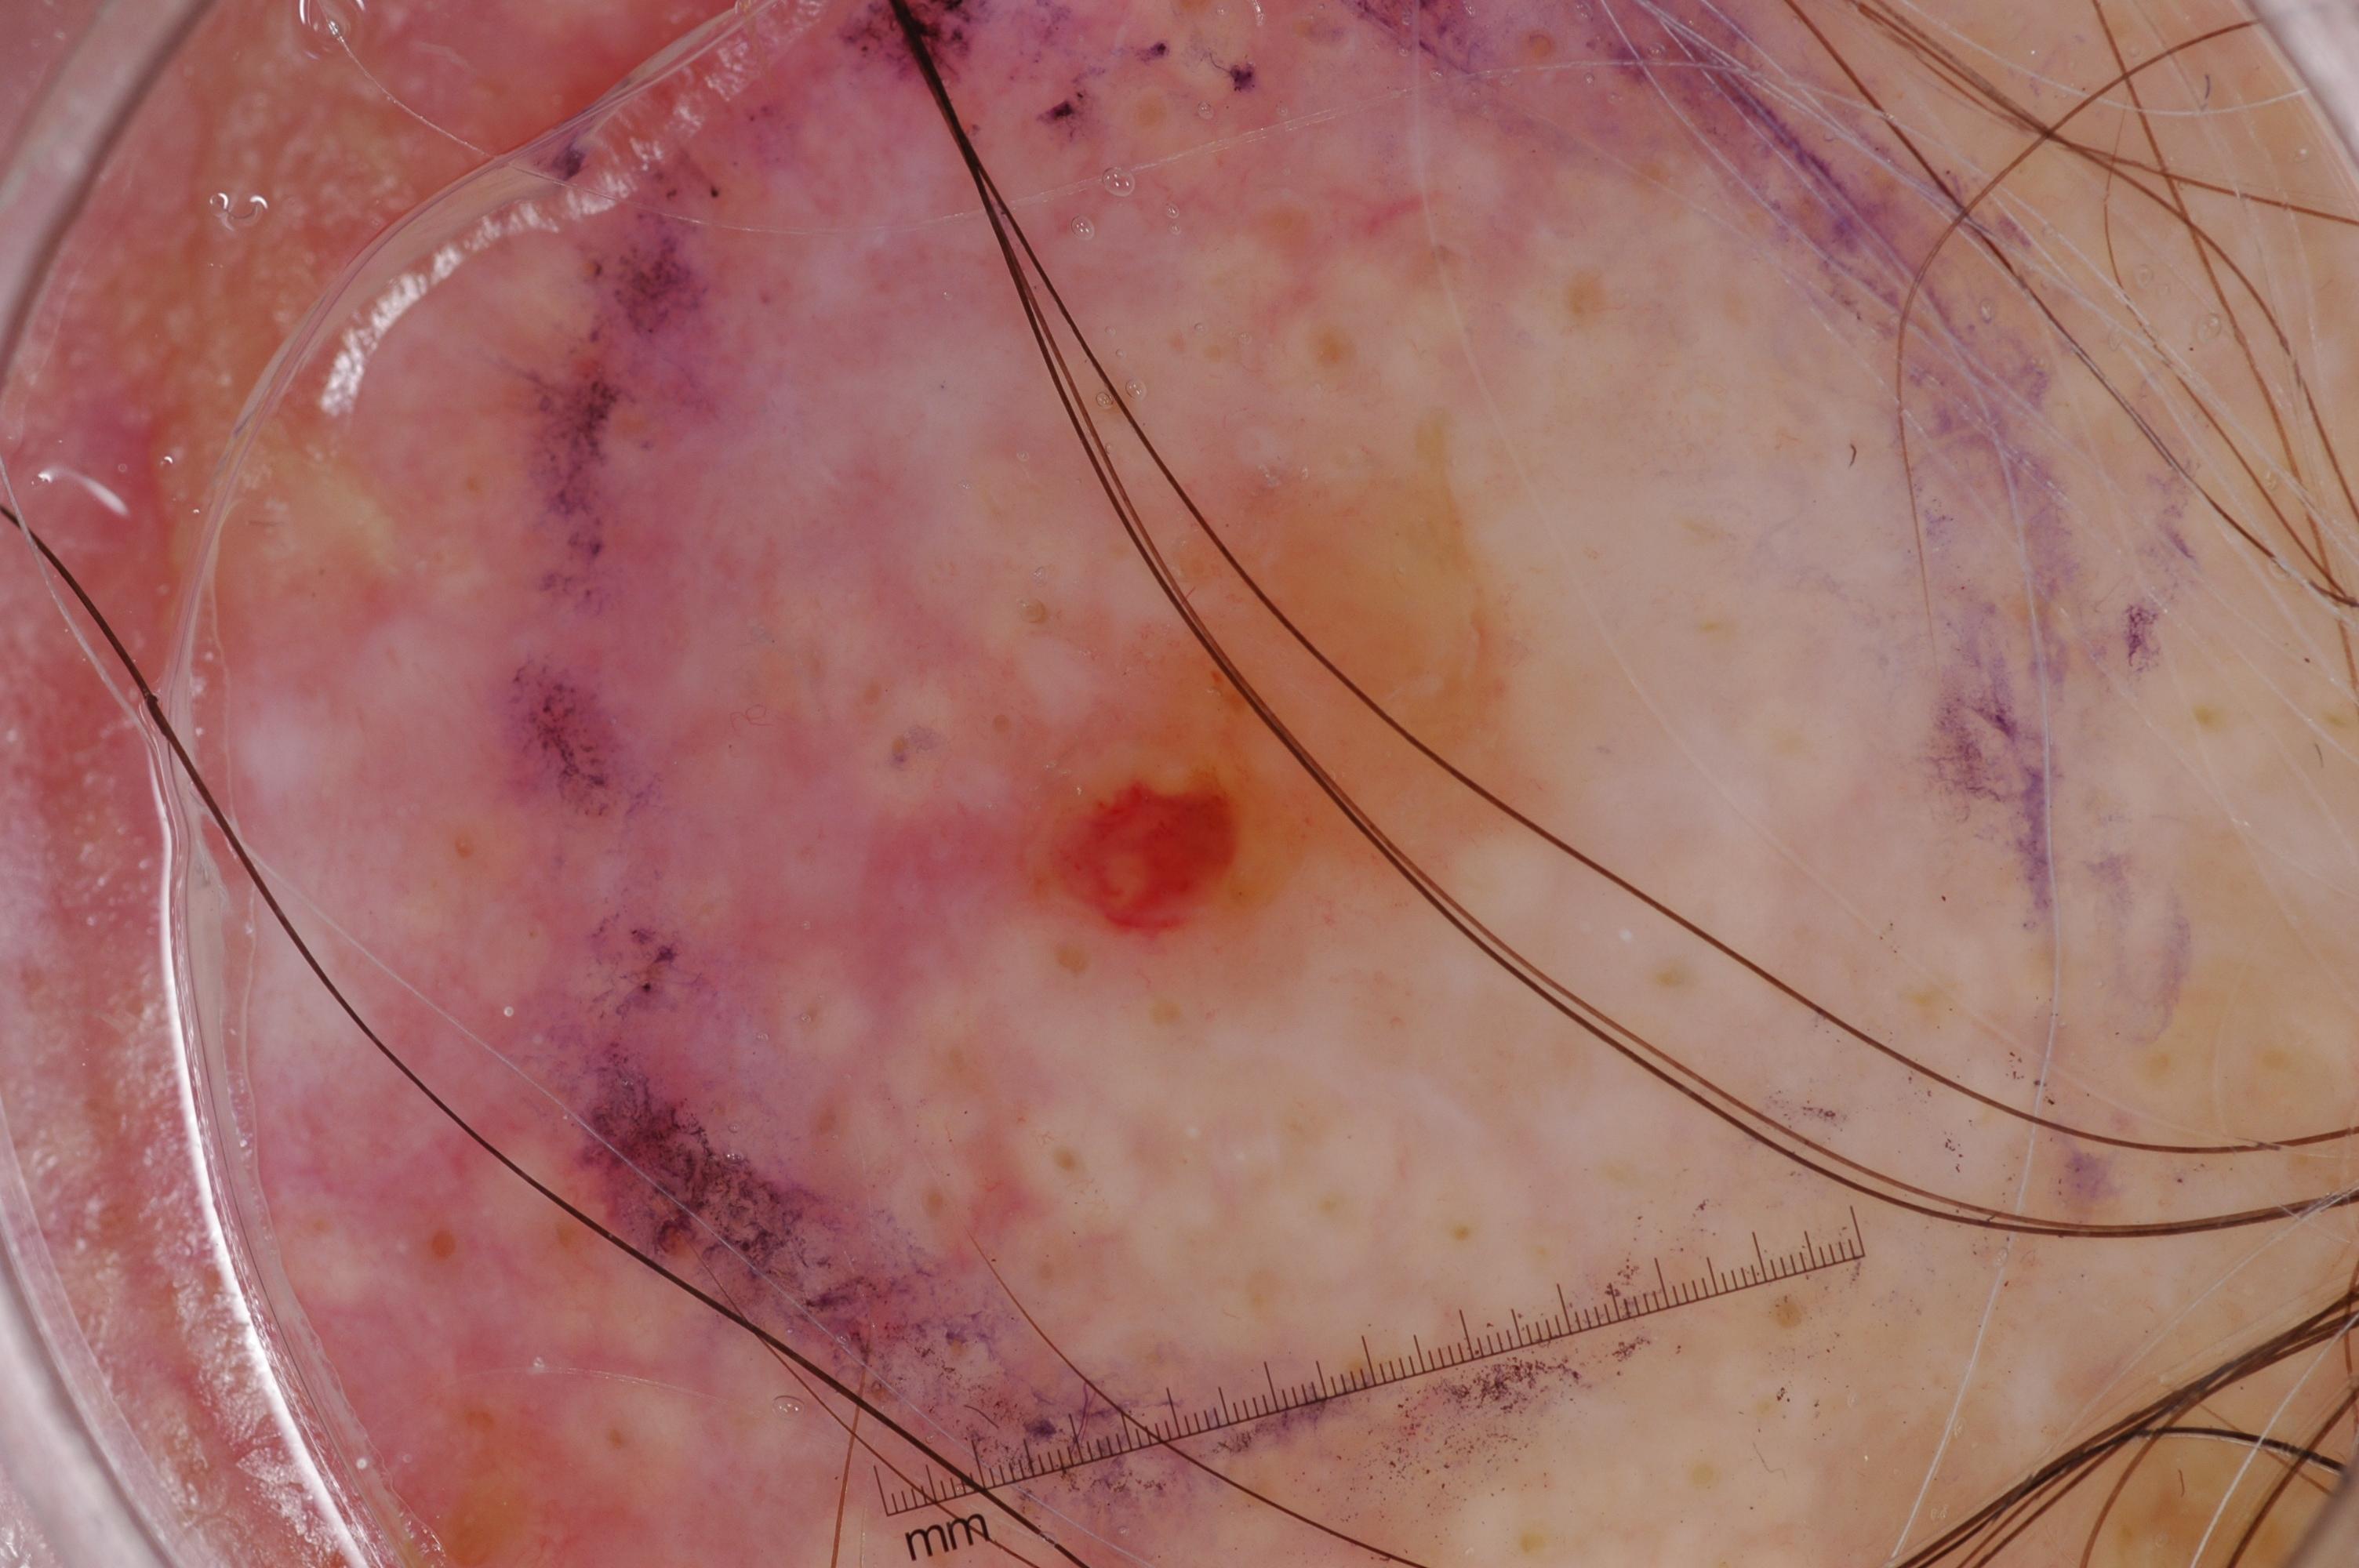

{

"age_approx": 60,

"anatom_site_general": "posterior torso",

"concomitant_biopsy": true,

"dermoscopic_type": "contact non-polarized",

"diagnosis_1": "Malignant",

"diagnosis_2": "Malignant melanocytic proliferations (Melanoma)",

"diagnosis_3": "Melanoma Invasive",

"diagnosis_confirm_type": "histopathology",

"image_type": "dermoscopic",

"lesion_id": "IL_1206610",

"melanocytic": true,

"sex": "female"

}